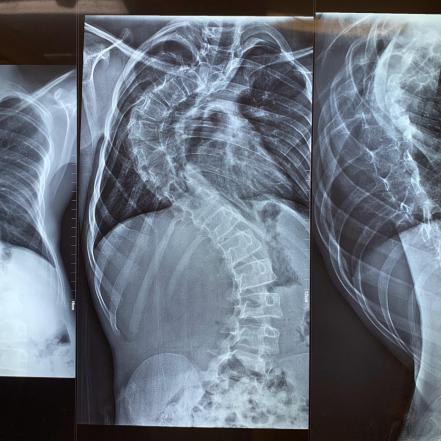

Por primera vez en la historia de México, se realizó en el Hospital General del ISSSTE de S.L.P. una cirugía de Escoliosis, una afectación en la columna vertebral, que forma una curvatura de que se presenta en forma de "S" o de "C".

El paciente, un masculino de 12 años de edad, fue intervenido por un equipo de 20 profesionales de la salud que durante más de 10 horas realizaron con éxito la intervención.

Cabe señalar que, debido a la complejidad de este procedimiento, muchos hospitales y Neurocirujanos del país no quisieron realizarla, sin embargo, bajo la dirección del Neurocirujano Dr. Onésimo Jaramillo, la Dra. Nora Saucedo y el Dr. Jorge Haro, médicos especialistas con larga y distinguida trayectoria, este histórico acontecimiento médico, logró llevarse a cabo con completo éxito.

El paciente, se encuentra en fase de recuperación y se espera que pronto pueda iniciar terapias de rehabilitación que le permitan mejorar su calidad de vida.